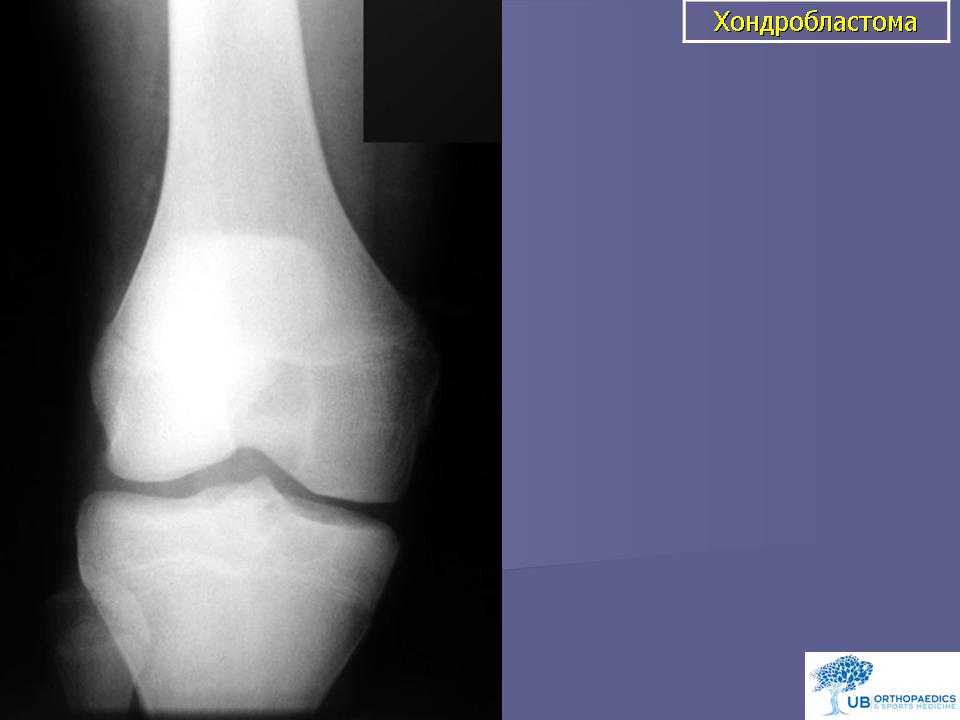

Рентгеновские снимки доброкачественных опухолей костей